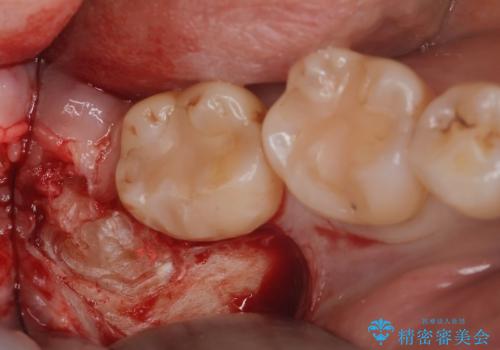

- 親知らずを抜歯したいとの事で来院。

パノラマ,CT撮影を行い安全なことを確認して抜歯を行いました。

抜歯後1週間後に抜糸と消毒を行い処置は完了になります。

- 外科手術のため、術後に出血、痛みや腫れ、違和感を伴います